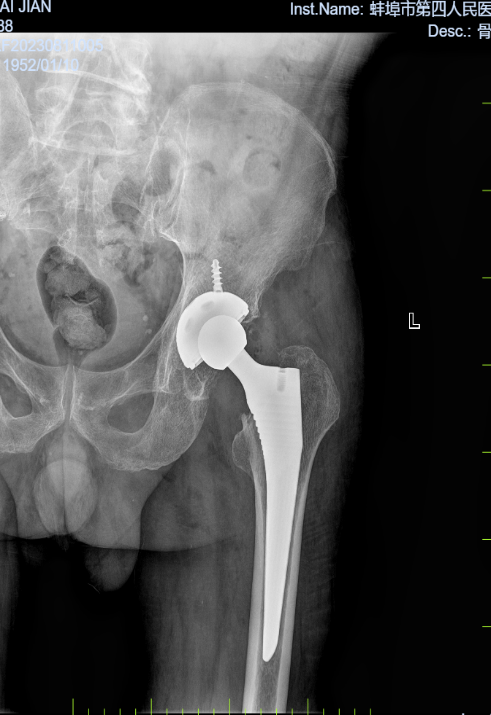

病例一:患者,男,71岁,因“左髋关节疼痛伴活动受限一周”入院。诊断:左侧股骨头无菌性坏死;行左侧全髋关节置换术,手术顺利,术后恢复良好,顺利出院。

左侧股骨头坏死 术前X线片 左侧股骨头坏死术后X线片